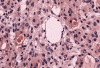

Histologic findings on  formalin fixed, paraffin sections of the specimen are very similar to that of the frozen sections (Panel K and L). The pseudonuclear inclusions are much better visualized in the paraffin section (Panel M). The core material in the microcysts is strongly PAS positive (Panel N). The tumor cells are focally positive for cytokeratin AE1/AE3 (Panel O) and positive for epithelial membrane antigen (EMA) (Panel P). Also unique to secretory meningioma is focally positive for carcinomembryonic antigen (CEA) (Panel Q).